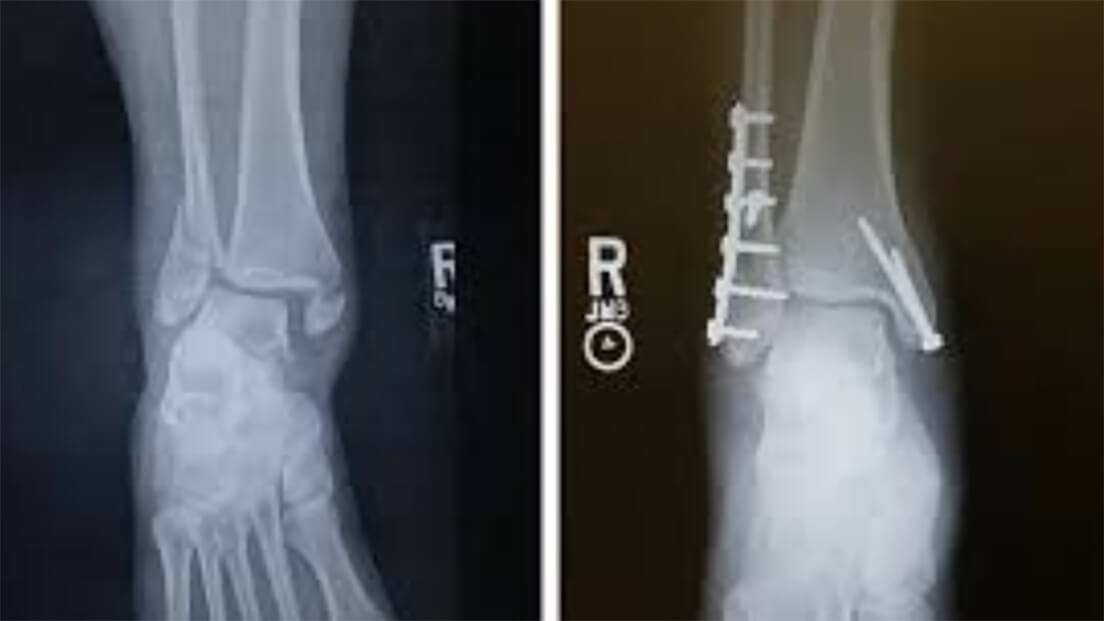

Let’s talk about trust for a second. It is through the personal contact, the questions and answers back and forth, the genuine concern displayed as they progress through a variety of injury specific skating drills and the determination to get them back that players will begin to trust in the person and the process. Hockey is a “people” business. The attached picture of the surgically repaired ankle is one example of a one-on-one on-ice process that built trust between the player and myself.

This injury was sustained by a 19-year-old Junior “A” player. Obvious that ROM, movement, and ability to load was going to be impacted. Day one on ice, he was visibly shaken and told me he would never play again. He simply could not turn right. Because we were together on ice, and I heard what he was saying, I was able to adjust what we were doing and convince him to trust the process. Long story short, he returned to play two more years and then went on to have a successful four-year NCAA career. It was trust that allowed for all that to happen. And trust only happened because I was present, listened to concerns and demonstrated that I was genuinely there to get him back.